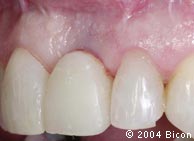

27. | 病人第二次就诊(种植体植入12周后),临时冠的唇侧观。 |

28. | 临时冠的唇侧观显示其牙龈发灰,是由于缺失颊侧骨板及牙龈组织较薄。 |